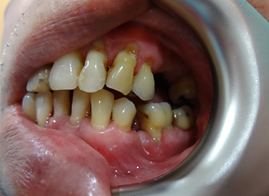

After the first therapy, there was total elimination of bad breathe and reduction in bleeding spot. Of course, I must complement his great effort in maintaining his oral hygiene. We repeated this procedure for another two times and review after 6 weeks, to allow gum healing. This is the result during review.

Gum appeared pinkish and healthy. No more gum bleeding, no more bad breathe, and teeth mobility was reduced. Clinical examination also showed great improvement. However, the lower front teeth are still loose, but no more bleeding.

We started to replace his missing teeth by implants after stabilising his gum condition. Throughout these years, x-ray were taken for implant placement and review purposes. Recent X-ray revealed bone regeneration at lower front region, and clinically his lower front teeth are firm after 2 years of the Periogreen photothermal therapy. We are both glad that we decided to keep his lower front teeth despite of the poor prognosis at that time.